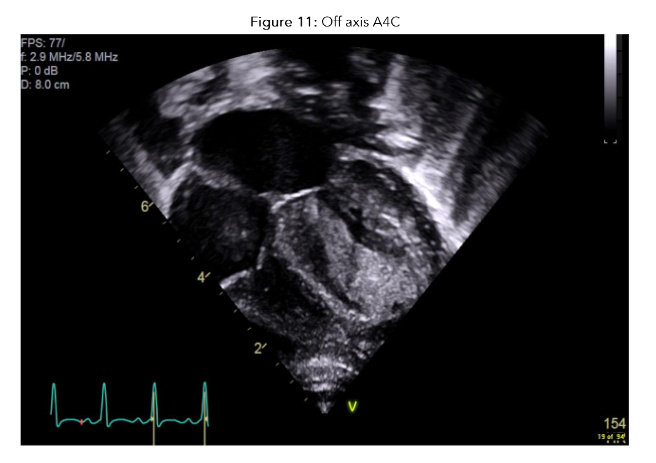

The boy was re-examined by a senior clinician following the initial survey and was noted to have a grade 3/6 ejection systolic murmur. Point of care echocardiogram was performed revealing a very large gelatinous mass occupying >50% of the left atrium.

Figure 9: PLAX view showing a very large gelatinous mass occupying >50% of the left atrium